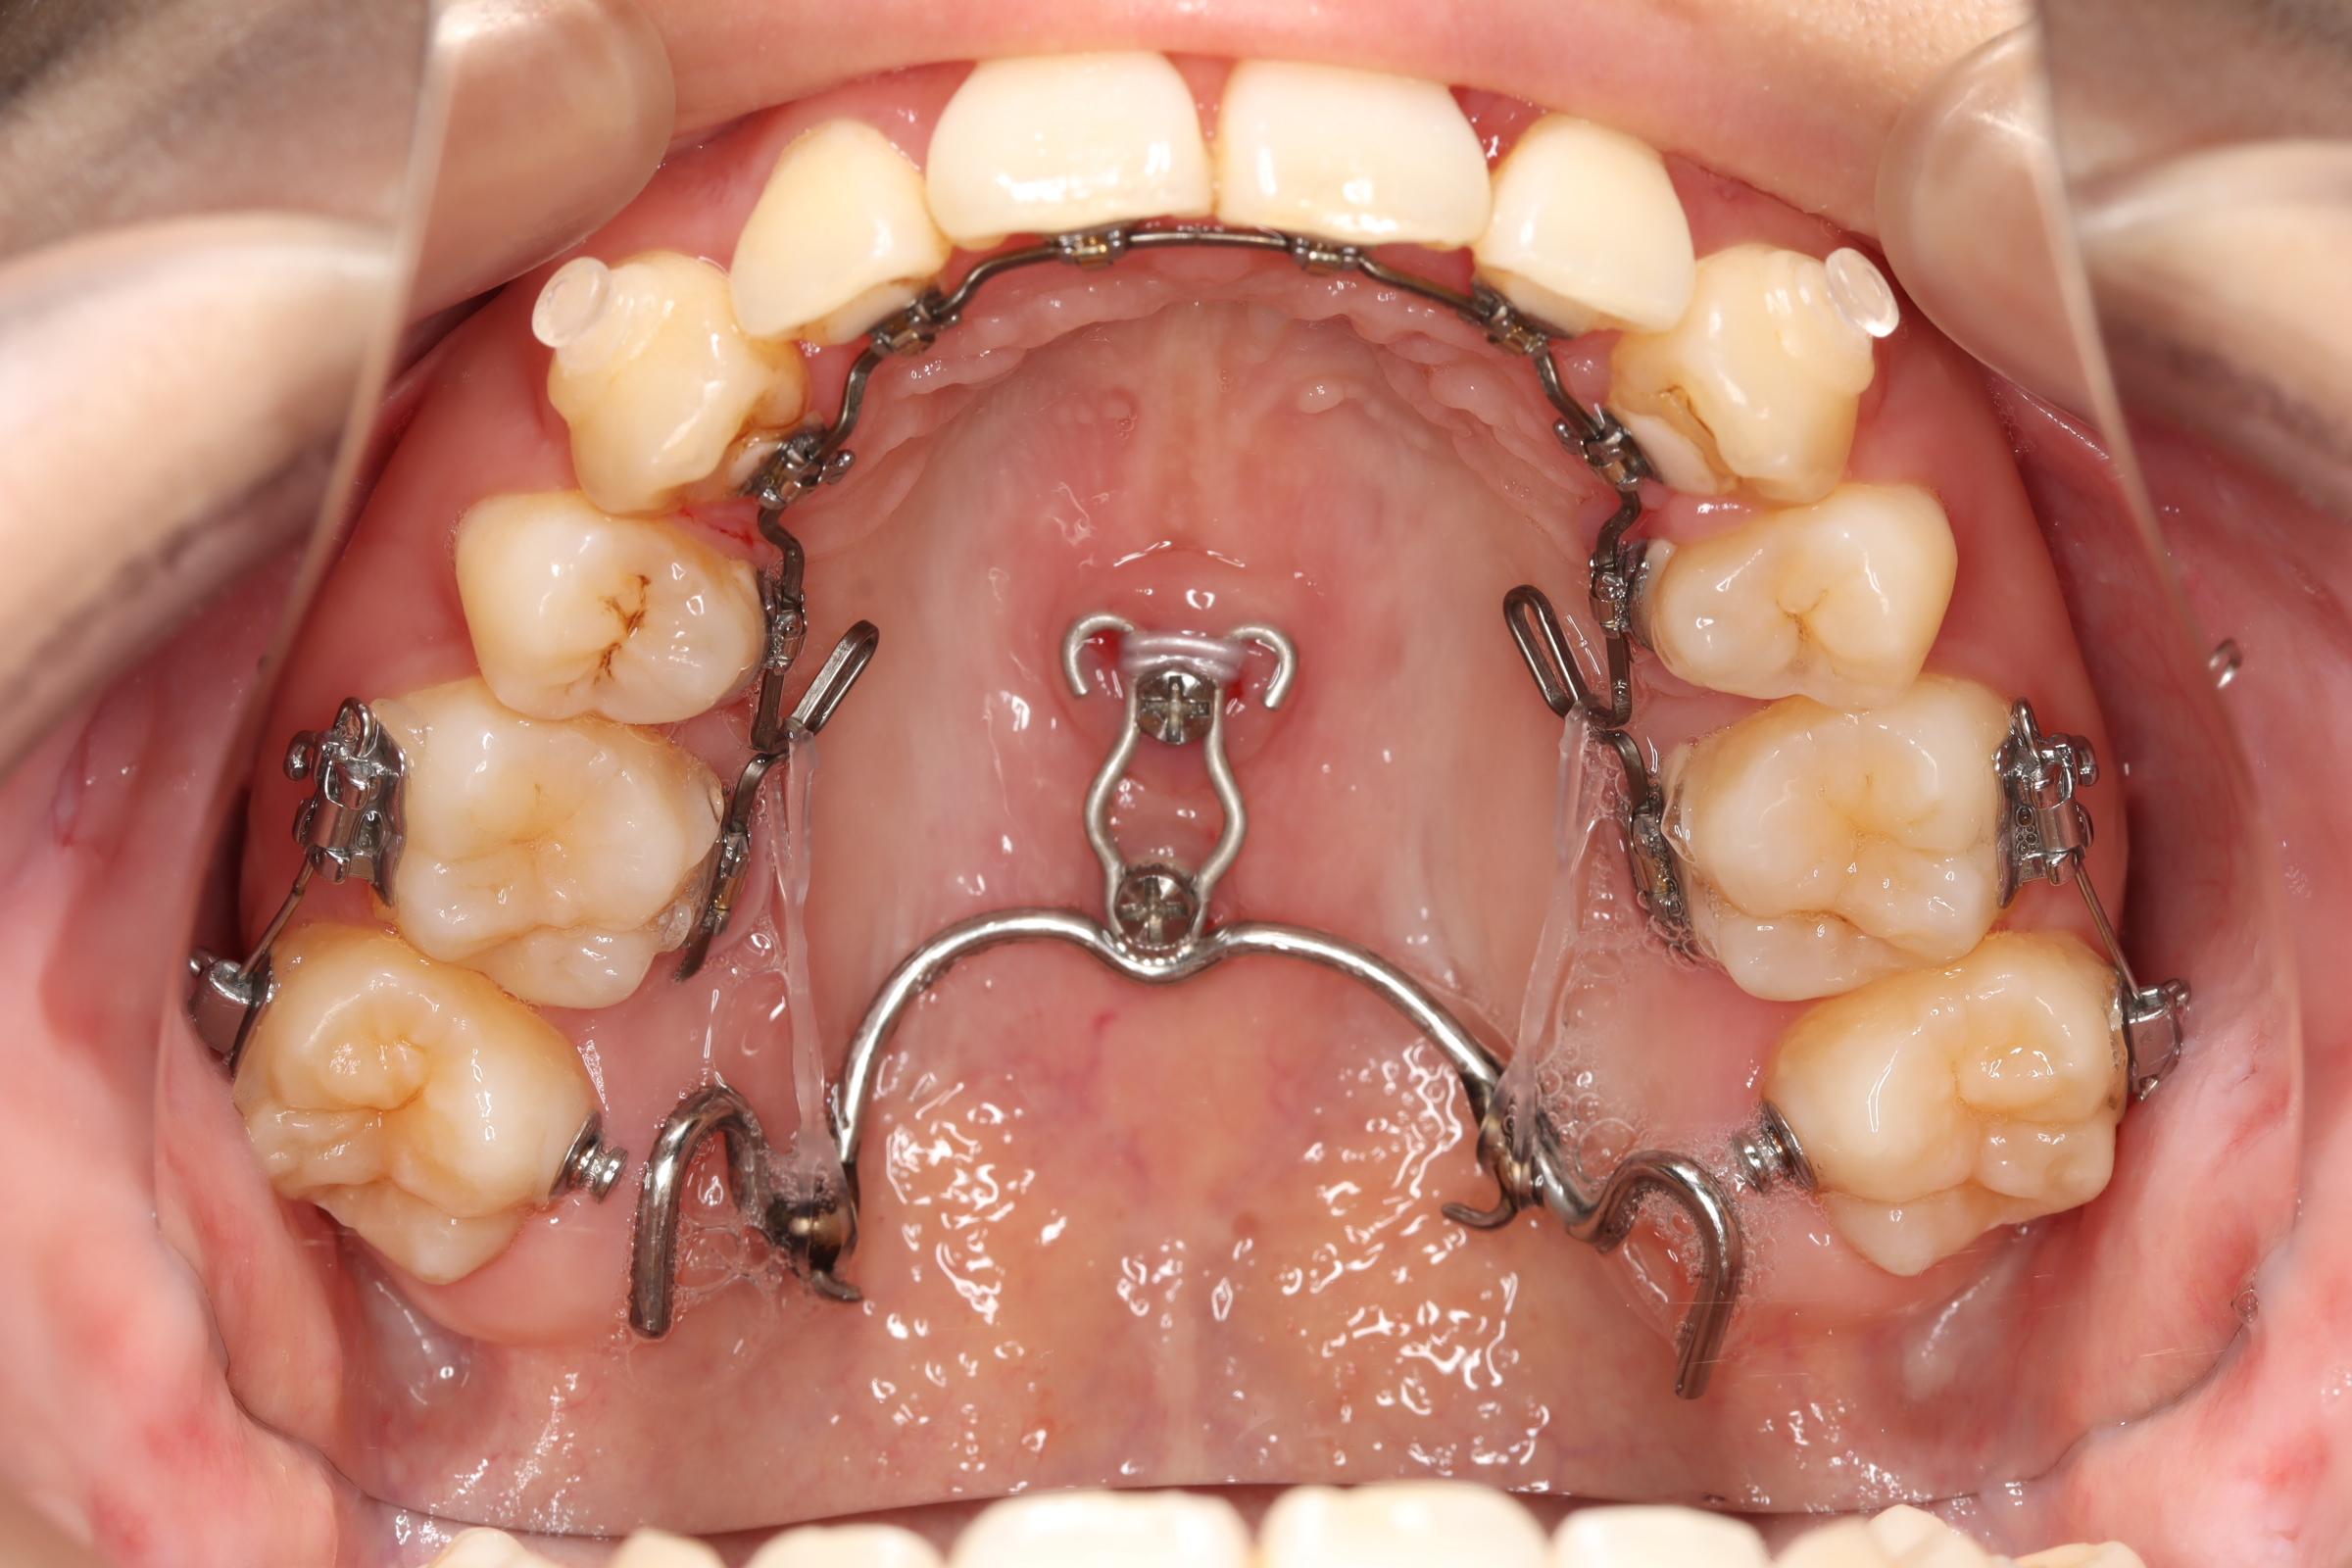

治療中

| ||

|  |  |

|

治療内容

| 使用矯正装置 | セルフライゲーションリンガルブラケット セルフライゲーションブラケット(セラミッククリッピー) 歯科矯正用アンカースクリュー |